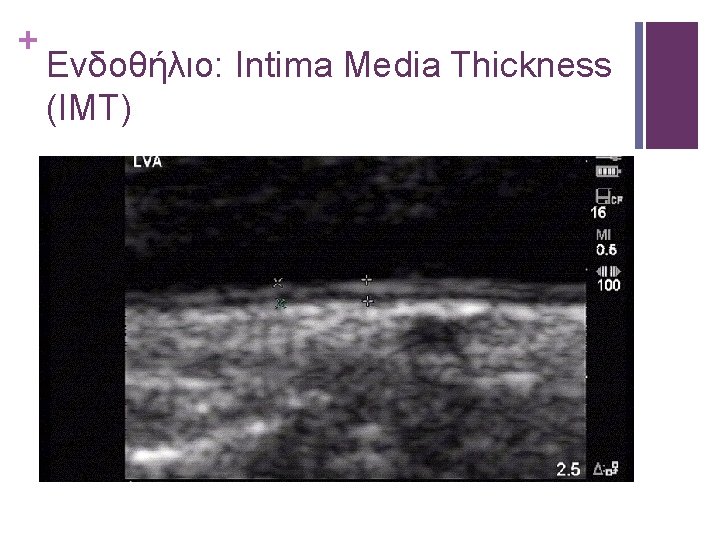

+ Ενδοθήλιο: Intima Media Thickness (IMT)